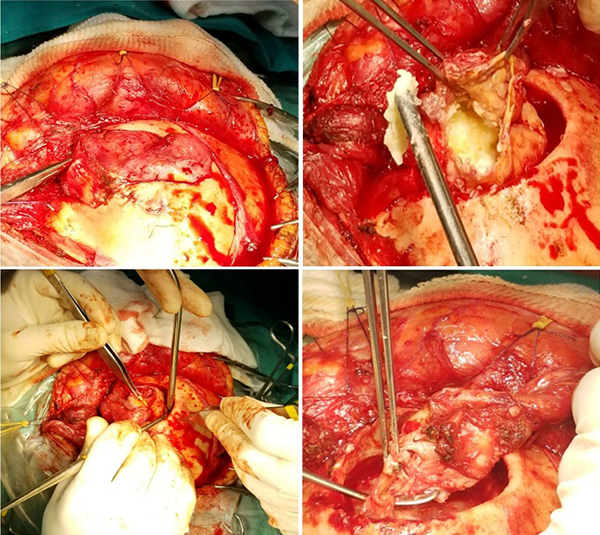

Debido a los hallazgos imagenológicos y clínicos, se decidió realizar su exéresis quirúrgica (Figuras 3 y 4).

Figura 3.

Imágenes intraoperatorias. Tiempo extradural.

Figura 4.

Imágenes intraoperatorias. Tiempo extra e intradural. Flecha amarilla: defecto dural a través del cual se comunica el espacio extra y subdural.

Se planificó un abordaje hemicoronal izquierdo pasante de línea media. El colgajo cutáneo se disecó en dos planos. Se constató el compromiso del plano subgaleal y de la fascia superficial del músculo temporal por parte de la lesión. La misma se disecó de forma circunferencial siguiendo su trayecto hacia su origen en la calota craneana y se obtuvo muestra de contenido del saco, el cual se describe como “blanco perlado”, de aspecto caseiforme, evacuándolo mediante aspiración en su totalidad. La cápsula tumoral detergida se disecó del borde óseo y la duramadre hasta rodear en 360° el sitio de perforación de la misma. Se realizó ligadura y exéresis del componente extradural del saco. Luego, se efectuó un fresado circunferencial del borde óseo, hasta observarlo sano.

El tiempo intradural se inició con la apertura dural centrada en el defecto de perforación a través de la cual se desprendió material caseoso de similares características al evacuado previamente. Se realizó lavado y aspiración de la cavidad intracerebral. Se visualizó una pseudocápsula friable sin plano de disección, lo que dificultó su exéresis completa a pesar del intento. Para finalizar, se llevó a cabo la exéresis de duramadre adelgazada e infiltrada, con posterior plástica dural con parche autólogo y se realizó un cierre cutáneo por planos.